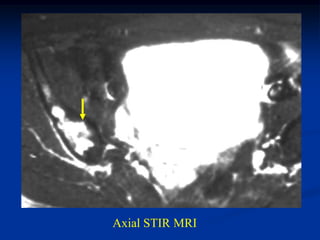

Case #215

22 year female

adamatinoma

distal tibia